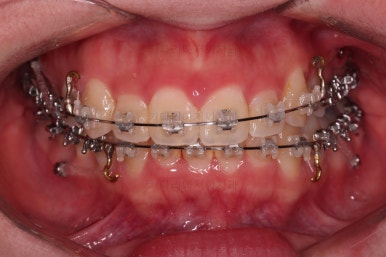

치열만 보면 매우 가지런해진 것 같죠?

이때가 대략 8개월 정도 지났을 때의 모습인데요.

어차피 비대칭은 수용해야 되고, 중앙서노 100% 안맞으니 이정도만 해도 매우 양호한 것 같죠?

하지만 해볼만한 치료는 상당히 많습니다.

이때쯤의 얼굴모습인데요.

여전히 돌출감이 있기 때문에 전 치열을 후방이동해서 입매를 개선해 주고요.

앞에서 봤을 때 치열은 가지런해졌지만 기울어진 느낌을 조금이라도 잡아보고자 미니스크류를 이용해서 입매 개선 및 기울기 개선을 시도했습니다.